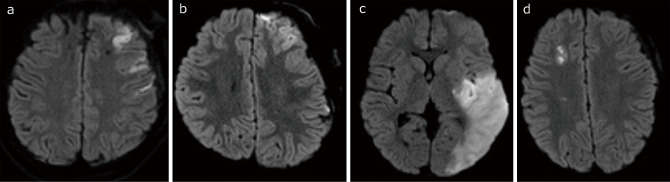

Pediatric patients with moyamoya disease frequently show rapid progression with a high risk of stroke. Indirect revascularization is widely accepted as a surgical treatment for pediatric moyamoya disease, but it does not augment cerebral blood flow immediately, which leaves patients at risk for stroke peri-operatively. This delay in flow augmentation may make adding direct bypass the better option. This study documents our cases of direct bypass failure that underwent indirect bypass supplemented with superficial temporal artery-middle cerebral artery bypass to evaluate the adverse effects of direct bypass failure. A retrospective review of all surgeries for pediatric moyamoya disease after introducing intraoperative indocyanine green videoangiography to confirm direct bypass patency identified 78 surgical hemispheres. Direct bypass failure was defined as failure to confirm blood flow from the superficial temporal artery to the middle cerebral artery on indocyanine green videoangiography. The occurrence of ischemic complications was evaluated by magnetic resonance imaging. During the period, postoperative ischemic complications were seen in 3 surgical hemispheres (3.8%) and one contralateral hemisphere (1.3%). One case in which hyperventilation was difficult to control postoperatively developed extensive cerebral infarction. Direct bypass failure was seen in 3 patients (3.8%), none of whom had additional cerebral infarction on magnetic resonance imaging. The results of this study indicate that failure of direct bypass surgery does not necessarily lead to cerebral infarction. Based on these results, surgeons can safely attempt to add a direct bypass to an indirect bypass, with special attention to perioperative patient management.

Abstract Image